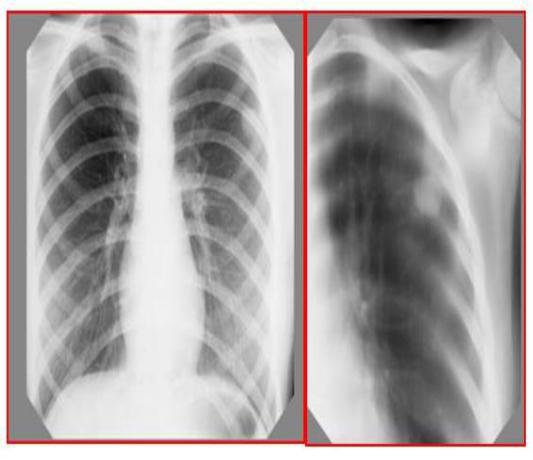

Иммунодиагностика: проба Манту 2 ТЕ – р. 12 мм, ДСТ – р. 4 мм Рентген - томографически: в верхней доле левого лѐгкого субплеврально

определяется неоднородное ограниченное затемнение округлой формы размерами 1,5×2,0 см.